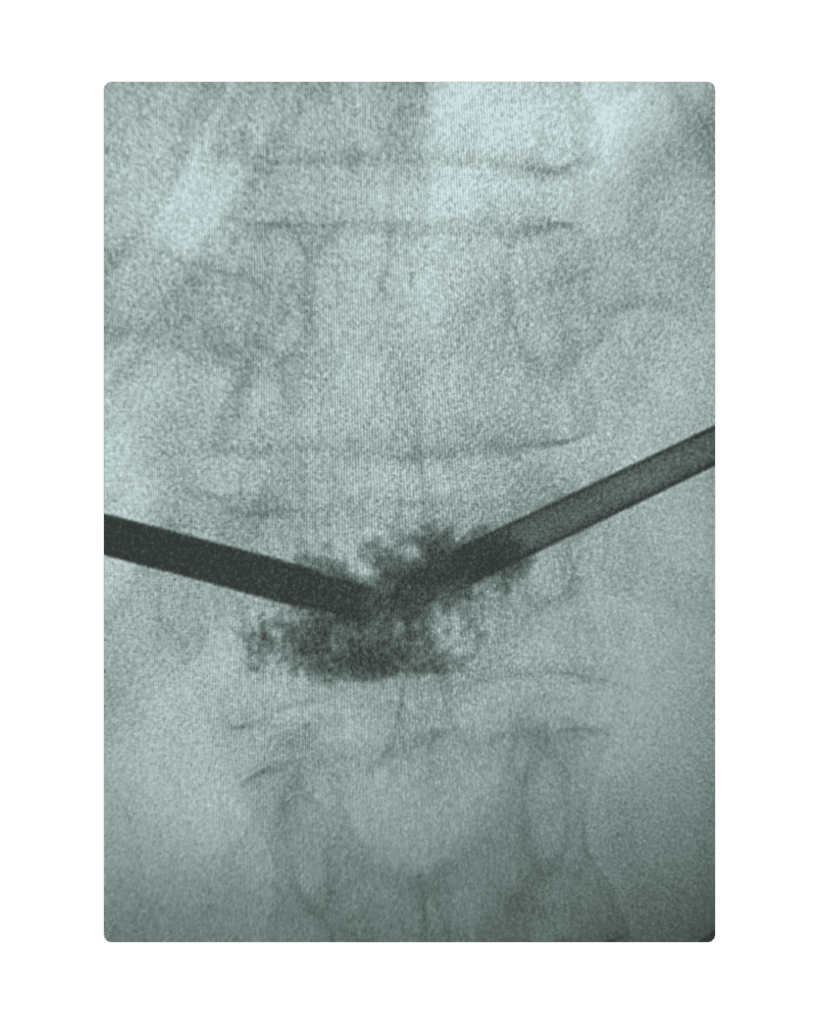

A minimally invasive vertebral cement augmentation (Kyphoplasty) was performed under local anaesthesia, providing :

A minimally invasive kyphoplasty performed under local anaesthesia provided safe and immediate pain relief, restoring mobility without exposing the patient to the risks of major surgery. This case highlights how interventional pain medicine can offer transformative outcomes even when surgical options are limited, reaffirming that restoring function and dignity is possible through thoughtful, multidisciplinary collaboration.